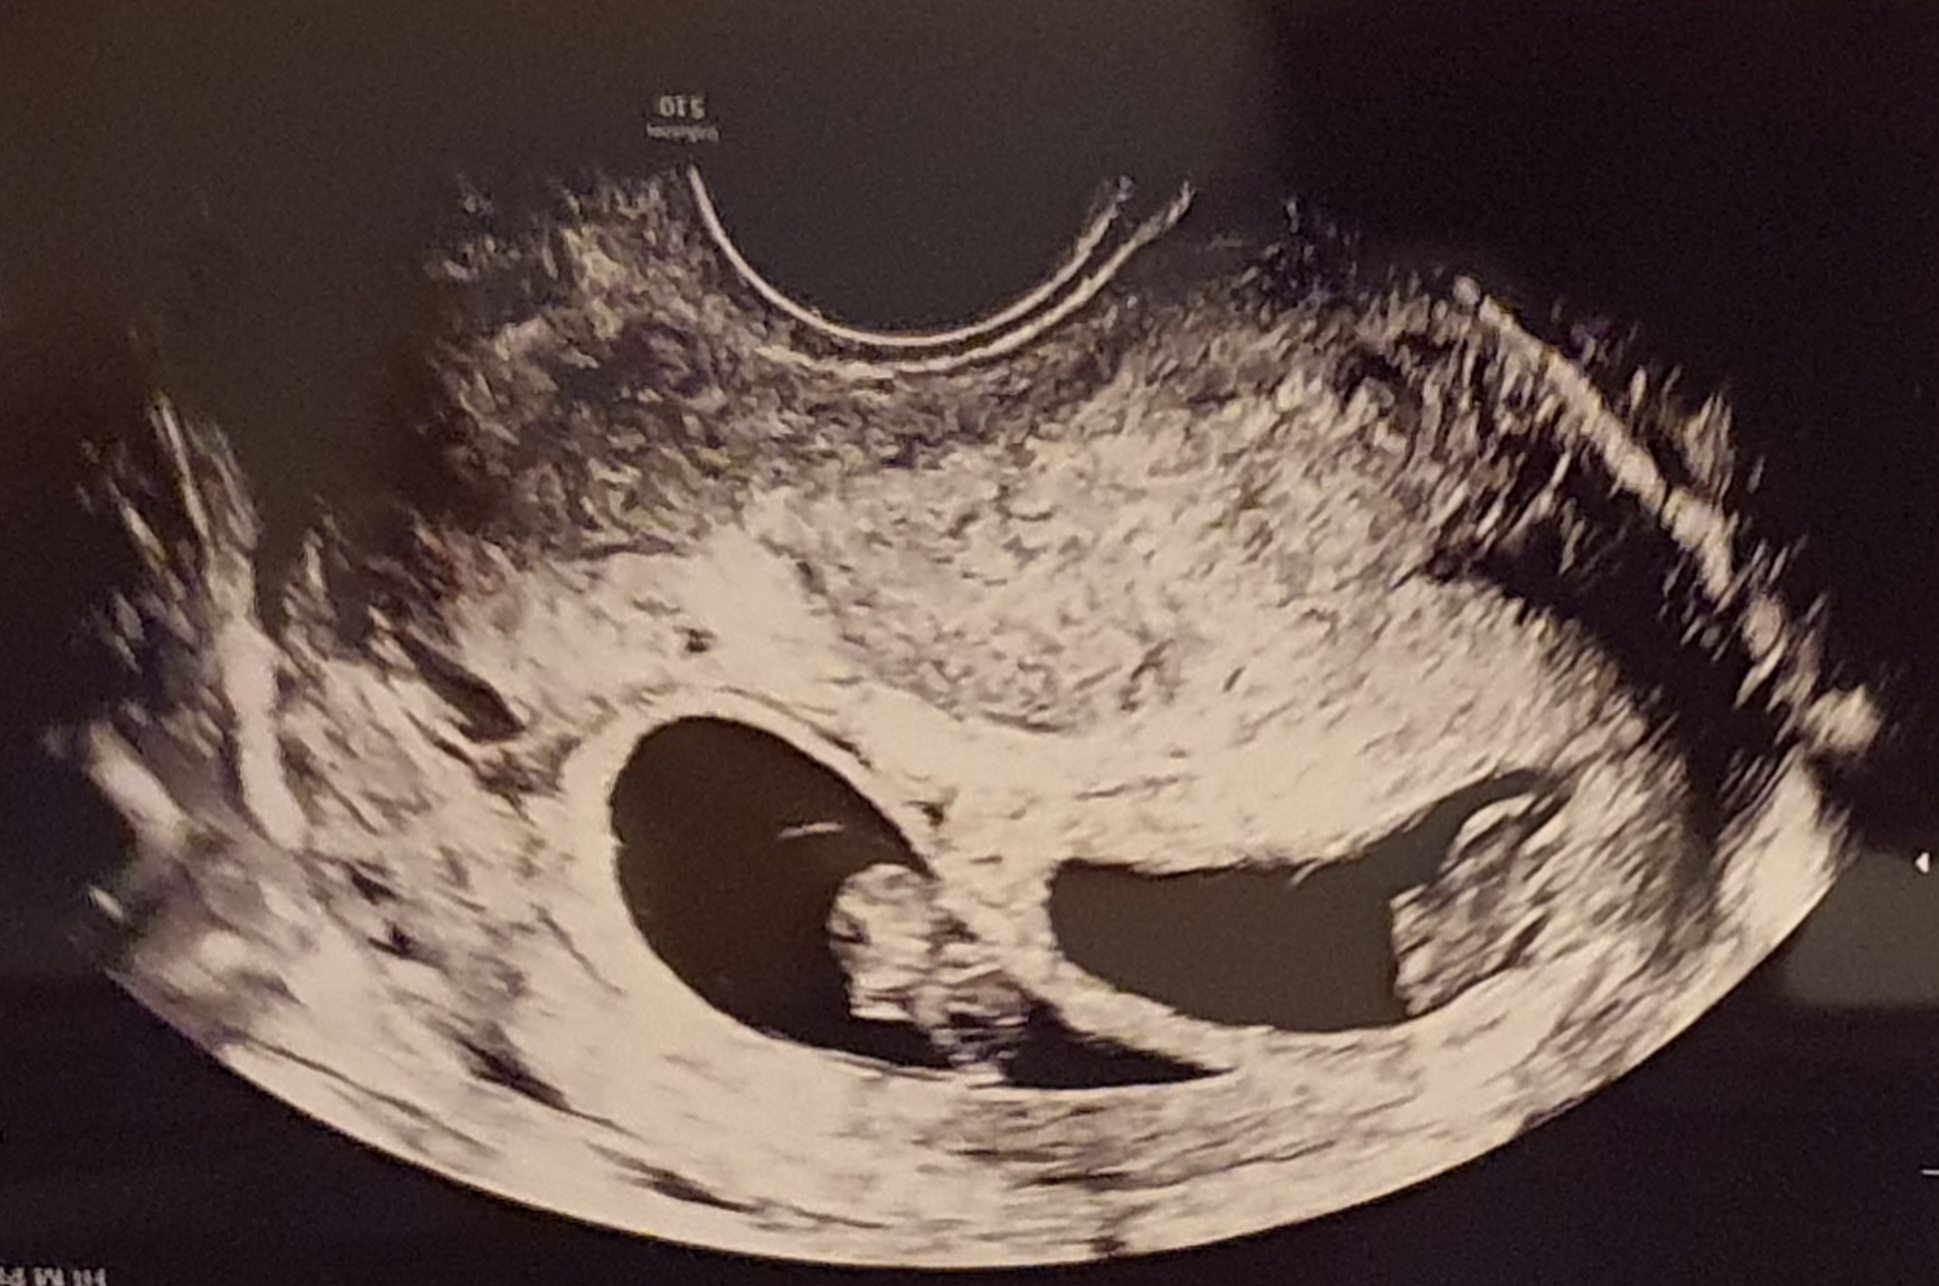

Byly ale chvíle - docela dlouhé období, kdy jsem prožívala beznaděj a smutek. Bála jsem se, že roli matky nikdy nezažiju. Cesta, kterou jsem prošla, byla klikatá a nejasná... Cesta s nespočtem zastávek, kterým jsem nerozuměla, byla plná bolesti a smutku.

Možná i ty máš pocit, že tvá cesta za dítětem je náročnější, než jsi si představovala. Pak věř, že jsi tady správně! Ráda budu právě já tvým průvodcem na této cestě.